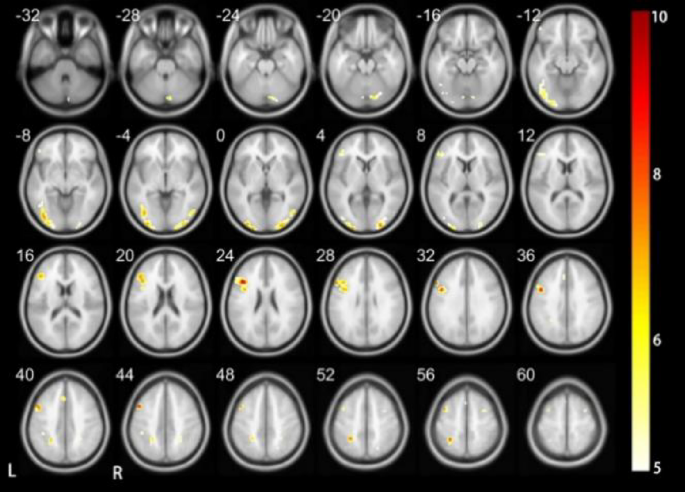

As depicted in Figs. 4 and 5; Tables 4 and 5, distinct patterns of neural activation were observed during the execution of the Vocal Tone 2 task in DC when compared to HC. Specifically, in DC, there was bilateral activation in the middle occipital gyrus, precentral gyrus, and supplementary motor area. These regions are critical for processing auditory and motor aspects of speech.

In contrast, HC demonstrated a more diverse pattern of activation. The right perisylvian cortex, left middle occipital gyrus, right middle temporal gyrus, left inferior frontal gyrus (triangular part), left precentral gyrus, right supplementary motor area, left middle frontal gyrus, and superior parietal gyrus are included. These findings indicate a broader neural engagement in the processing of vocal tones, possibly reflecting the integration of auditory, motor, and linguistic information.

Upon comparative analysis, notable differences in neural activation patterns were observed between the two groups. DC did not exhibit activation in several key areas associated with language processing and auditory perception, including the perisylvian cortex, middle temporal gyrus, triangular part of the inferior frontal gyrus, middle frontal gyrus, and superior parietal gyrus. Conversely, for regions such as the middle occipital gyrus, precentral gyrus, and supplementary motor area, there was bilateral activation in DC, whereas in HC, activation was predominantly observed in the left hemisphere. These discrepancies underscore the adaptive changes in neural processing strategies employed by DC in the perception and execution of vocal tones. The bilateral activation patterns in DC suggest a compensatory mechanism that may facilitate tone recognition and production in the absence of typical auditory input. Valuable insights into the neural plasticity associated with auditory deprivation and its implications for speech and language development have been provided.